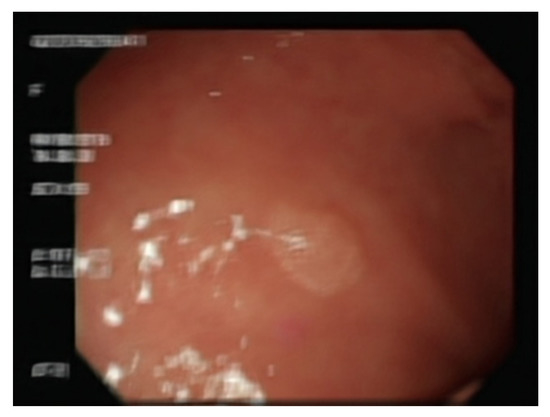

4.1. Comparison of GAN-Generated Images

4.2. Comparison of YOLO Using Different Datasets